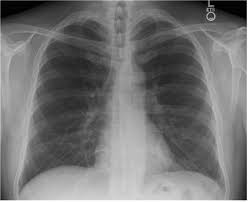

기흉을 가장 손쉽게 진단하는 방법은 흉부 X-선 사진입니다. 위에 언급한 증상을 보이는 환자를 흉부 X-선 사진으로 촬영하면, 대부분 쉽게 기흉을 진단할 수 있습니다. 환자에 대한 진찰 소견으로 진단하는 방법도 있습니다. 병변 부위의 타진상, 공명과도(hyperresonance) 소견, 청진상 호흡음의 감소 소견 등으로 기흉을 의심할 수 있습니다. 흉부 X-선 촬영을 진행하고 전문가가 판독하여 기흉을 확진합니다.

최근에는 흉부 전산화 폐단층촬영(HRCT)등을 시행하여 진단, 치료 방침의 설정에 이용합니다. 그 목적은 선택적인 기흉 환자에게 수술 치료가 필요한지 확인하는 것입니다. 하지만 이 검사는 모든 환자에게 필요하지 않으므로, 전문가와 상의해야 합니다.